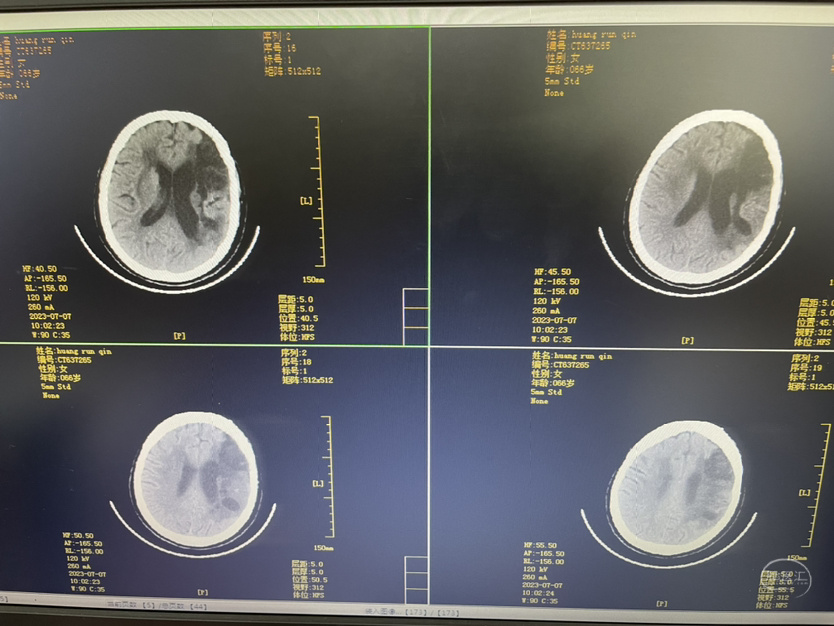

工作笔记:

HRQ、女,66岁,463177,因头昏头疼2天,吐词不清1天于20230203日16时24分入院。右侧肢体肌力四级。

术后第一天

术后第三天

术后第五天

术后第十一天

术后第一个月

夹闭术后两个月,出院后一个月!再次出血,血肿量大,患者清醒!转上级市级医院,拟予介入栓塞后清除血肿

家属选择保守治疗,患者一直清醒!两个月前在华西行介入栓塞术,血肿吸收!

介入栓塞术后两个月来复查!患者清醒轮椅而来,言语稍含糊,右侧下肢肌力可大于三级,上肢一级!